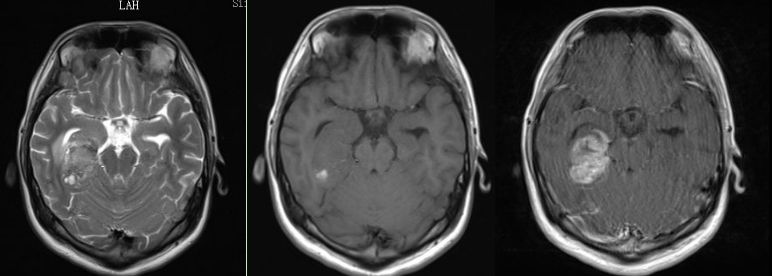

外引流术后症状稍改善。外引流术后3天复查头颅 MRI:

1. 右侧海马异常强化影,部分软脑膜播散转移可能。

2. 幕上脑积水伴间质性水肿。

3. 左侧额顶枕叶、右侧丘脑及侧脑室旁新发梗塞灶考虑(图7)。

图7. 头颅 MRI:1. 右侧海马异常强化影,部分软脑膜播散转移可能。 2.幕上脑积水伴间质性水肿。 3.左侧额顶枕叶、右侧丘脑及侧脑室旁新发梗塞灶考虑。